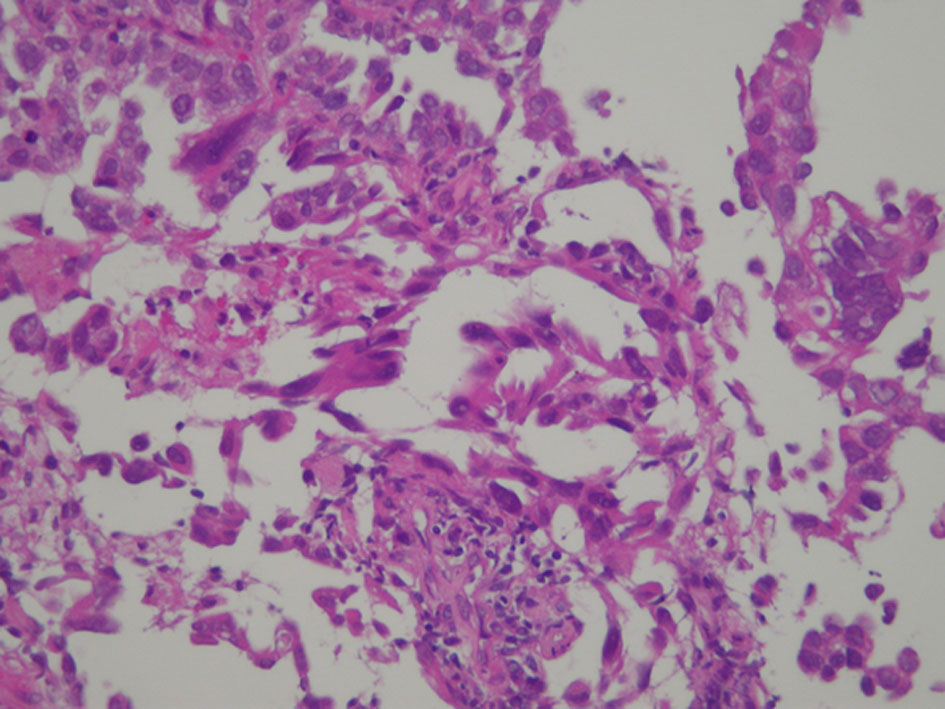

A 58-year-old man was referred to our department because of a tumor shadow in the right middle lung field in April 2010, and presented with a 2-month history of intermittent bloody sputum. He was an ex-smoker with 35 pack-year smoking history, and had no significant medical history except for hypertension. Chest CT showed an 80 × 40 mm sized sub-pleural tumor and multiple intrapulmonary nodules in the right lung. The right hilar, mediastinal and supraclavicular lymph nodes were swollen. He was diagnosed as lung adenocarcinoma by bronchoscopical biopsy from the right B3b (Fig. 6). The clinical stage was c-stage IIIB (cT3N3M0). No EGFR mutation was found in the bronchoscopical specimen by PCR clamp method. Because of the tiny residual specimen, neither ALK nor other mutation could not be examined. The first-line chemotherapy of four courses of induction carboplatin (AUC 6 mg/mL/min, day 1) and pemetrexed (500 mg/m2, day 1) provided PR, but the following two courses of pemetrexed maintenance resulted in progression of the primary tumor, intrapulmonary metastases and multiple mediastinal lymphadenopathies. The second-line of docetaxel (60 mg/m2, day 1) achieved PR temporarily. However, 2 months after the completion of four courses of docetaxel, multiple brain metastases appeared (Fig. 7a, b). Theses metastases successfully disappeared by erlotinib (150 mg/day, every day), which was initiated as the third-line chemotherapy in March 2011 (Fig. 7c, d). Erlotinib was reduced to 100 mg/day in March 2013 because of progressive polymyalgia, which might be retrospectively a prodromal symptom of polycythemia vera. We tried stopping erlotinib in March 2020, because no recurrence had been found for 9 years after the initiation of erlotinib. However, 3 months after the discontinuation of erlotinib, a solitary metastasis appeared in the left temporal lobe (Fig. 7e). He received GKR at another hospital in July 2020, and then resumed erlotinib in August 2020. Hydroxycarbamide (500 mg/day, 3 days/week) was started by hematologists in October 2020 for polycythemia vera harboring JAK2V617 mutation, when peripheral leukocyte count was continuously over 70,000 cells/µL. Thereafter, he continued combination of hydroxycarbamide and erlotinib, and no recurrence of lung cancer had been found in October 2022, 11 years and 8 months after the start of erlotinib. He experienced grade 4 of retroperitoneal hemorrhage in January 2020, grade 3 of intramuscular hematoma in the left femoral muscle in May 2015, grade 2 of skin hyperpigmentation, paronychia and multiple compression fractures.

![]() Click for large image | Figure 6. Histology of bronchoscopical specimen of case 2 (H&E stain). H&E: hematoxylin and eosin. |